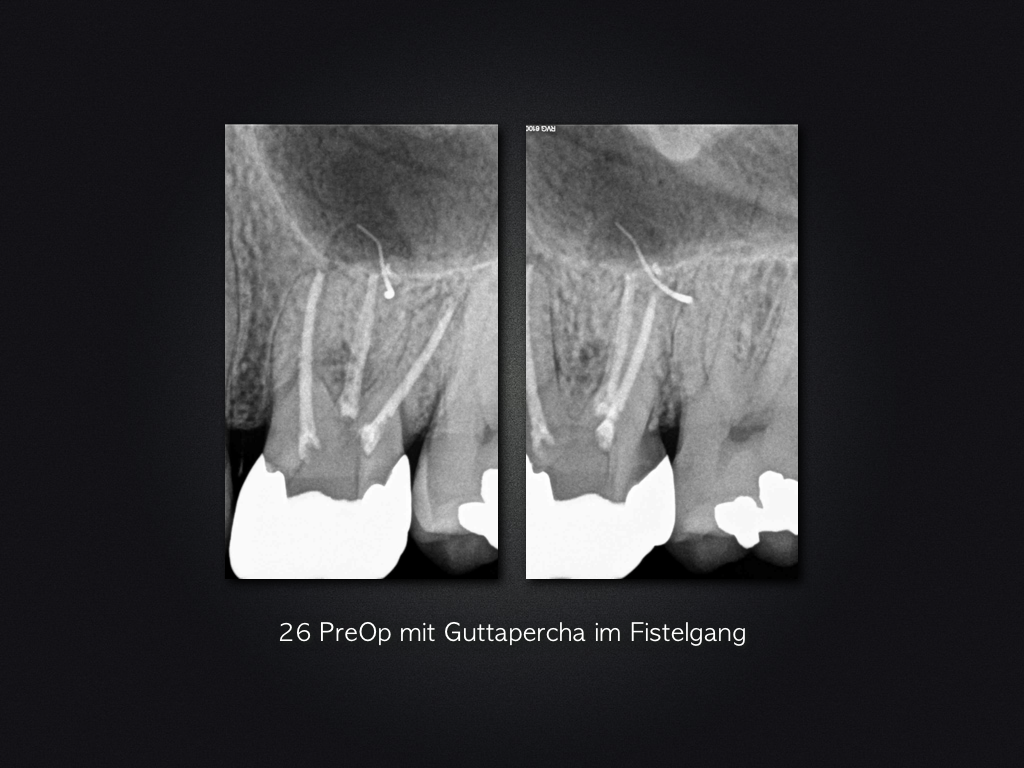

2D vs. 3D (XXV)